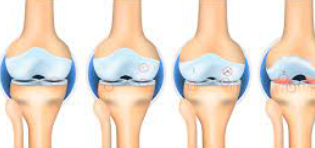

연골 손상 정도별 증상 변화

1단계: 경미한 연골 손상 증상

연골 손상 초기 단계에서는 증상이 미미하여 단순한 피로나 근육통으로 오인하기 쉽습니다. 주요 증상으로는 운동 후 가벼운 무릎 불편감, 아침 기상 시 약간의 강직감, 날씨 변화에 따른 무릎 불편감 등이 있습니다.

이 단계에서는 일상생활에 큰 지장이 없어 대부분 간과하게 되지만, 적절한 관리가 이루어지지 않으면 손상이 진행될 수 있습니다. 따라서 가벼운 증상이라도 지속되면 전문의 상담을 받는 것이 중요합니다.

2단계: 중등도 연골 손상 증상

연골 손상이 중등도로 진행되면 증상이 더욱 뚜렷해집니다. 계단 오르내리기, 쪼그려 앉기, 장시간 걷기 등의 활동에서 명확한 통증이 나타납니다. 무릎 관절에서 소리가 자주 나며, 무릎을 완전히 구부리거나 펴는 것이 어려워집니다.

이 단계에서는 무릎 부종이 눈에 띄게 나타나며, 활동 후 무릎이 무겁고 뻣뻣한 느낌이 지속됩니다. 진통제를 복용해야 할 정도의 통증이 발생하며, 수면 중에도 무릎 때문에 잠을 깨는 경우가 생깁니다.

3단계: 심각한 연골 손상 증상

연골 손상이 심각한 단계에 이르면 일상생활에 심각한 지장을 초래합니다. 평지 보행에서도 통증이 발생하며, 무릎을 움직일 때마다 심한 통증과 함께 관절음이 지속적으로 나타납니다.

무릎 관절의 변형이 육안으로도 확인되며, 무릎이 완전히 펴지지 않거나 구부러지지 않는 관절 강직이 나타납니다. 무릎에 힘이 빠지는 느낌과 함께 관절 불안정성이 심화되어 넘어질 위험이 증가합니다.